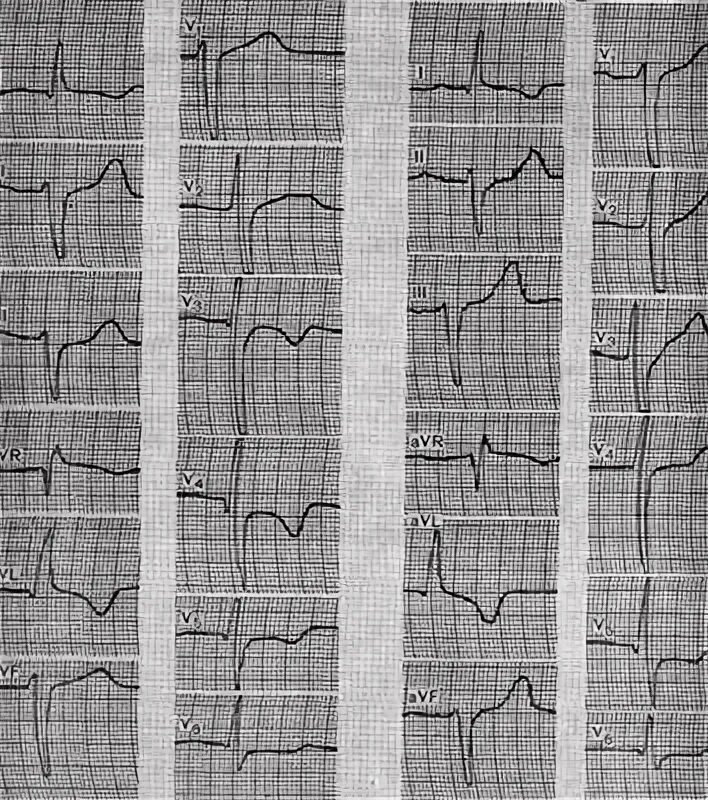

Рубцовые изменения в миокарде